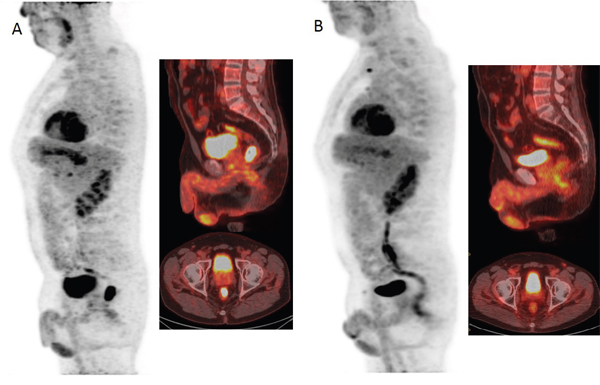

Figure 1a shows ROC analysis for ΔSIS and ΔSUVmax in discriminating responders from non responders. The optimal cut-off for ΔSIS was a reduction of 6.0% yielding 92.7% of sensitivity and 80.0% of specificity to identify responder patients. Instead, the optimal cut-off of 59.7% for ΔSUVmax showed lower accuracy in identifying responder patients than ΔSIS, with a sensitivity of 67.3% and a specificity of 75.0%. 55 patients were classified as responders by ΔSIS, including 51 true positives, while 41 patients were classified as responders by ΔSUVmax, including 37 true positives. The combination of ΔSIS and ΔSUVmax did not increase predictive ability, classifying 43 patients as responders, of whom only 36 were true pathological responders. Figure 1b shows ROC analysis for ΔSIS and ΔSUVmax in discrimination pathological complete response (TRG1) by incomplete response (TRG 2-4). The optimal cut-off for ΔSIS was a reduction of 30.3% (93.3% of sensitivity and 68.9% of specificity) while the optimal cut-off of 43.9% for ΔSUVmax showed lower accuracy (sensitivity of 80.0% and specificity of 31.1%). Statistically significant differences between ΔSIS and ΔSUVmax, in terms of both sensitivity and specificity, were assessed using the McNemar test (p value <0.05), for both analysis. The presurgical PET/CT analysis demonstrated a low level of correlation between median ΔSUVmax value with pT and TRG findings (Spearman's rank correlation coefficient = -0.2 and -0.3, respectively), while a good level of correlation was observed between median ΔSIS value and pT and between median ΔSIS value and TRG (Spearman's rank correlation coefficient = -0.6 and -0.7, respectively). Table 3 shows the performance of ΔSIS and ΔSUV analysis to identify responder from non-responder patients and complete by incomplete pathological response. Figures 2 and 3 show DCE-MRI and 18F-FDG PET/CT images respectively, for a responder patient (TRG = 1). Figures 4 and 5 respectively show DCE-MRI and 18F-FDG PET/CT images, for another responder patient (TRG = 2)recognized only to ΔSIS analysis.

Figure 3: 18F-FDG PET/CT images before A and after B treatment showed a reduction of FDG uptake with a ΔSUVmax of 96.67% classifying the patient as responder.